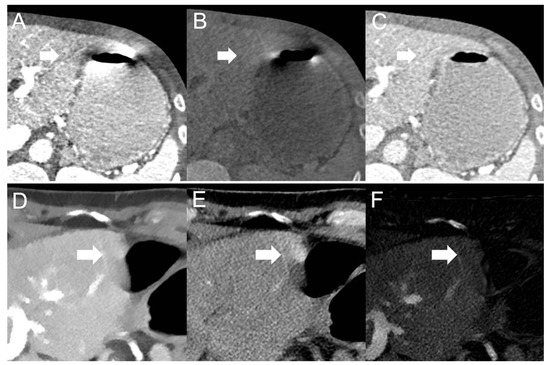

- Fast kV-switching scanner: Depth of extension of visceral-motion-related artifacts into the liver was significantly shorter (p < 0.001, each) for iodine (mean length: 6 ± 7 mm) images compared with 120-kVp-like (mean length: 11 ± 7 mm), 40-keV (mean length: 9 ± 8 mm), 140-keV (mean length: 10 ± 8 mm), and VNC (mean length: 13 ± 8 mm) images. Mean ROI measurements were significantly different in the bright and dark artifact components compared to unaffected liver parenchyma in 120-kVp-like (p < 0.001, each), 40-keV (p < 0.001, each), 140-keV (p < 0.001, each), VNC (p < 0.001, each), and iodine images (p < 0.001, each).

- Dual-layer spectral detector scanner: Depth of extension of visceral-motion-related artifacts into the liver was significantly shorter (p < 0.001, each) for iodine (mean length: 2 ± 5 mm) images compared with 120-kVp (mean length: 11 ± 5 mm), 40-keV (mean length: 10 ± 6 mm), 200-keV (mean length: 11 ± 5 mm), and VNC (mean length: 11 ± 5 mm) images. Mean ROI measurements were significantly different in the bright and dark artifact components compared to unaffected liver parenchyma in 120-kVp (p < 0.001, each), 40-keV (p < 0.001, each), 200-keV (p < 0.001, each), and VNC (p < 0.001, each) images. However, in iodine images mean ROI measurements were not significantly different in bright (ROImax) artifact components compared to unaffected liver parenchyma (p = 0.15), as opposed to dark (ROImin) artifact components (p < 0.001). Further details on quantitative artifact measurements are provided in Table 2 and the Supplementary Material.

- Fast kV-switching scanner: Qualitative artifact scores were significantly lower (p < 0.001, each) for iodine images (median score: 2, range: 1–5) compared with 120-kVp-like (median score: 3, range: 1–5), 40-keV (median score: 3, range: 1–5), 140-keV (median score: 3, range: 1–5), and VNC (median score: 3, range: 1–5) images.

- Dual-layer spectral detector scanner: Qualitative artifact scores were significantly lower (p < 0.001, each) for iodine images (median score: 1, range: 1–3) compared with 120-kVp (median score: 3, range: 1–5), 40-keV (median score: 3, range: 1–5), 200-keV (median score: 3, range: 2–5), and VNC (median score: 3, range: 1–5) images. Further details on qualitative artifact scores are provided in the Supplementary Material.